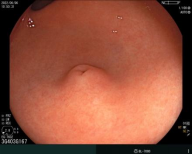

胃内粘膜下隆起,术前超声提示来源于固有肌层,术前判断需胃壁全层切除。

术中所见与术前判断相符,行内镜全层切除术EFTR,术后严密封闭创面,患者2日后安全出院,术后病理诊断胃间质瘤。